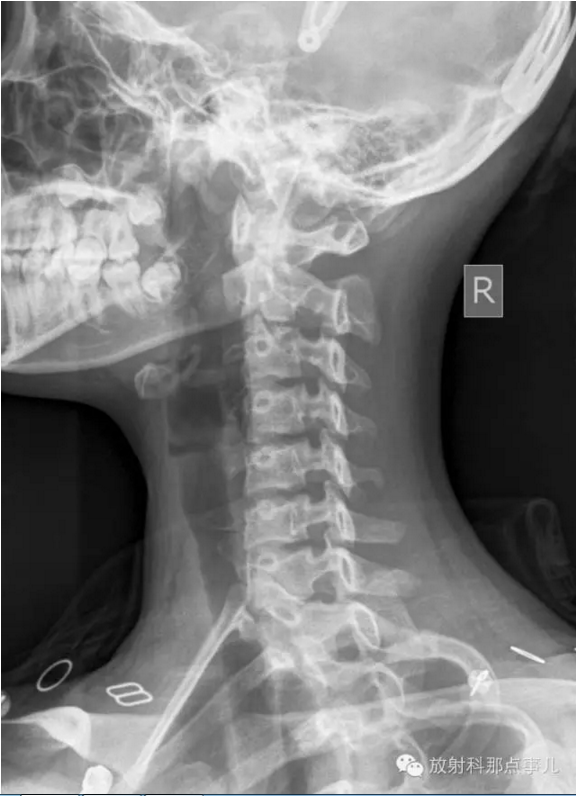

1、张口位

观察有无寰枢关节脱臼,齿状突骨折或缺失(张口位片);第七颈椎横突有无过长,有无颈肋。钩椎关节及椎间隙有无增宽和狭窄。